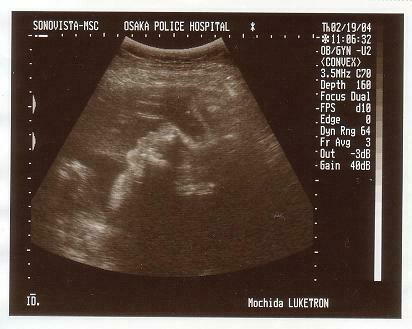

<第五回超音波検査>

2月19日の検査の写真です。妊娠8ヶ月目です。この2週間

前に伊勢に旅行に行ったり、赤ちゃんグッズをそろそろ買い始

めたりしていました。家内のお腹もかなり前に突き出してきて、

俊介も「ボコ!ボコ!」とお腹を内側から蹴るようになります。

写真ですが逆から見たらわかりやすいのですが、俊介の横顔で

す。かなり大きくなっているので、超音波では部分部分しか確

認することしかできません。

この頃俊介は逆子の状態で、夜寝る前に家内は逆子体操をずっ

と行っておりました。